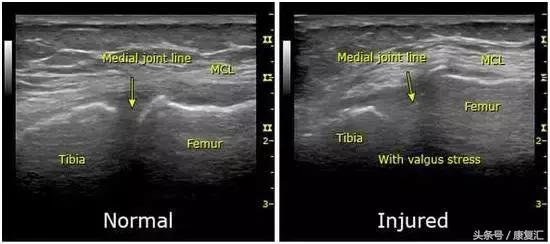

内侧副韧带损伤后临床表现为膝关节内侧肿痛,皮下瘀血,膝关节活动受限,损伤处有明显的压痛点,小腿外展时疼痛加剧,侧向分离试验阳性。医生用手检查也可以确诊,再经核磁共振(MRI)进一步确定韧带损伤的程度,通过MRI检查可以把损伤分为3个级别:

1级:膝关节内侧副韧带纤维轻度撕裂,可见韧带周围水肿或血肿信号,无关节不稳定,病变不明显;

2级:浅层膝关节内侧副韧带完全撕裂,可见韧带部分中断或增厚,出现膝关节不稳定;

3级:浅层和深层膝关节内侧副韧带完全断裂,韧带内异常高信号,关节不稳定明显。